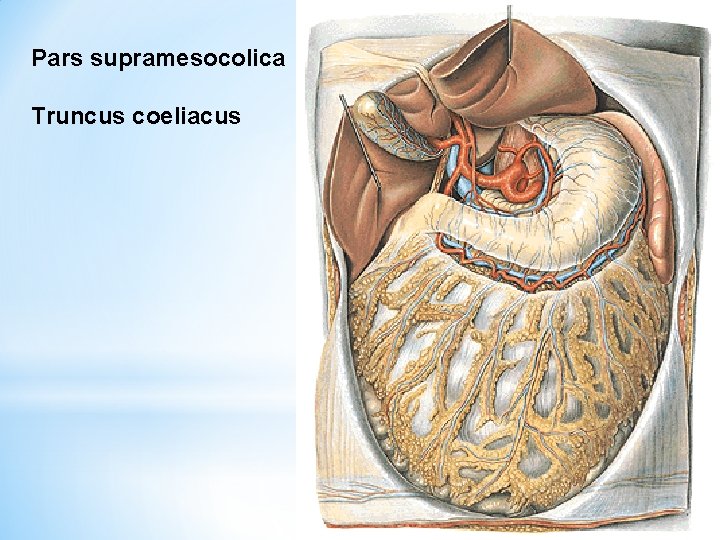

Pars supramesocolica Truncus coeliacus